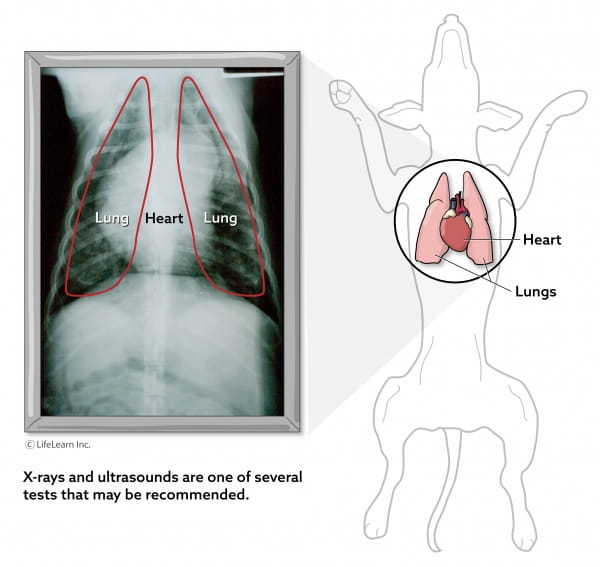

This area can become inflamed for several reasons as the condition known as mediastinitis is a complication of several diseases and disorders. Most appear on the chest flanks legs and neck. Lipomas - fatty skin lumps that often start very soft and become firmer as they grow. These soft rounded non-painful masses that usually present just under the skin are generally benign. The mid-chest area in dogs is known as the mediastinum and contains the heart the central bronchi and the lymph nodes.

Lipomas are harmless lumps that start in fat cells stored in tissue around the body and are not usually painful. Theyre made up entirely of fat cells and are always benign or non-cancerous. What is a lipoma and what causes it. The mid-chest area in dogs is known as the mediastinum and contains the heart the central bronchi and the lymph nodes. They are more common in middle age to older dogs and have certain characteristics.